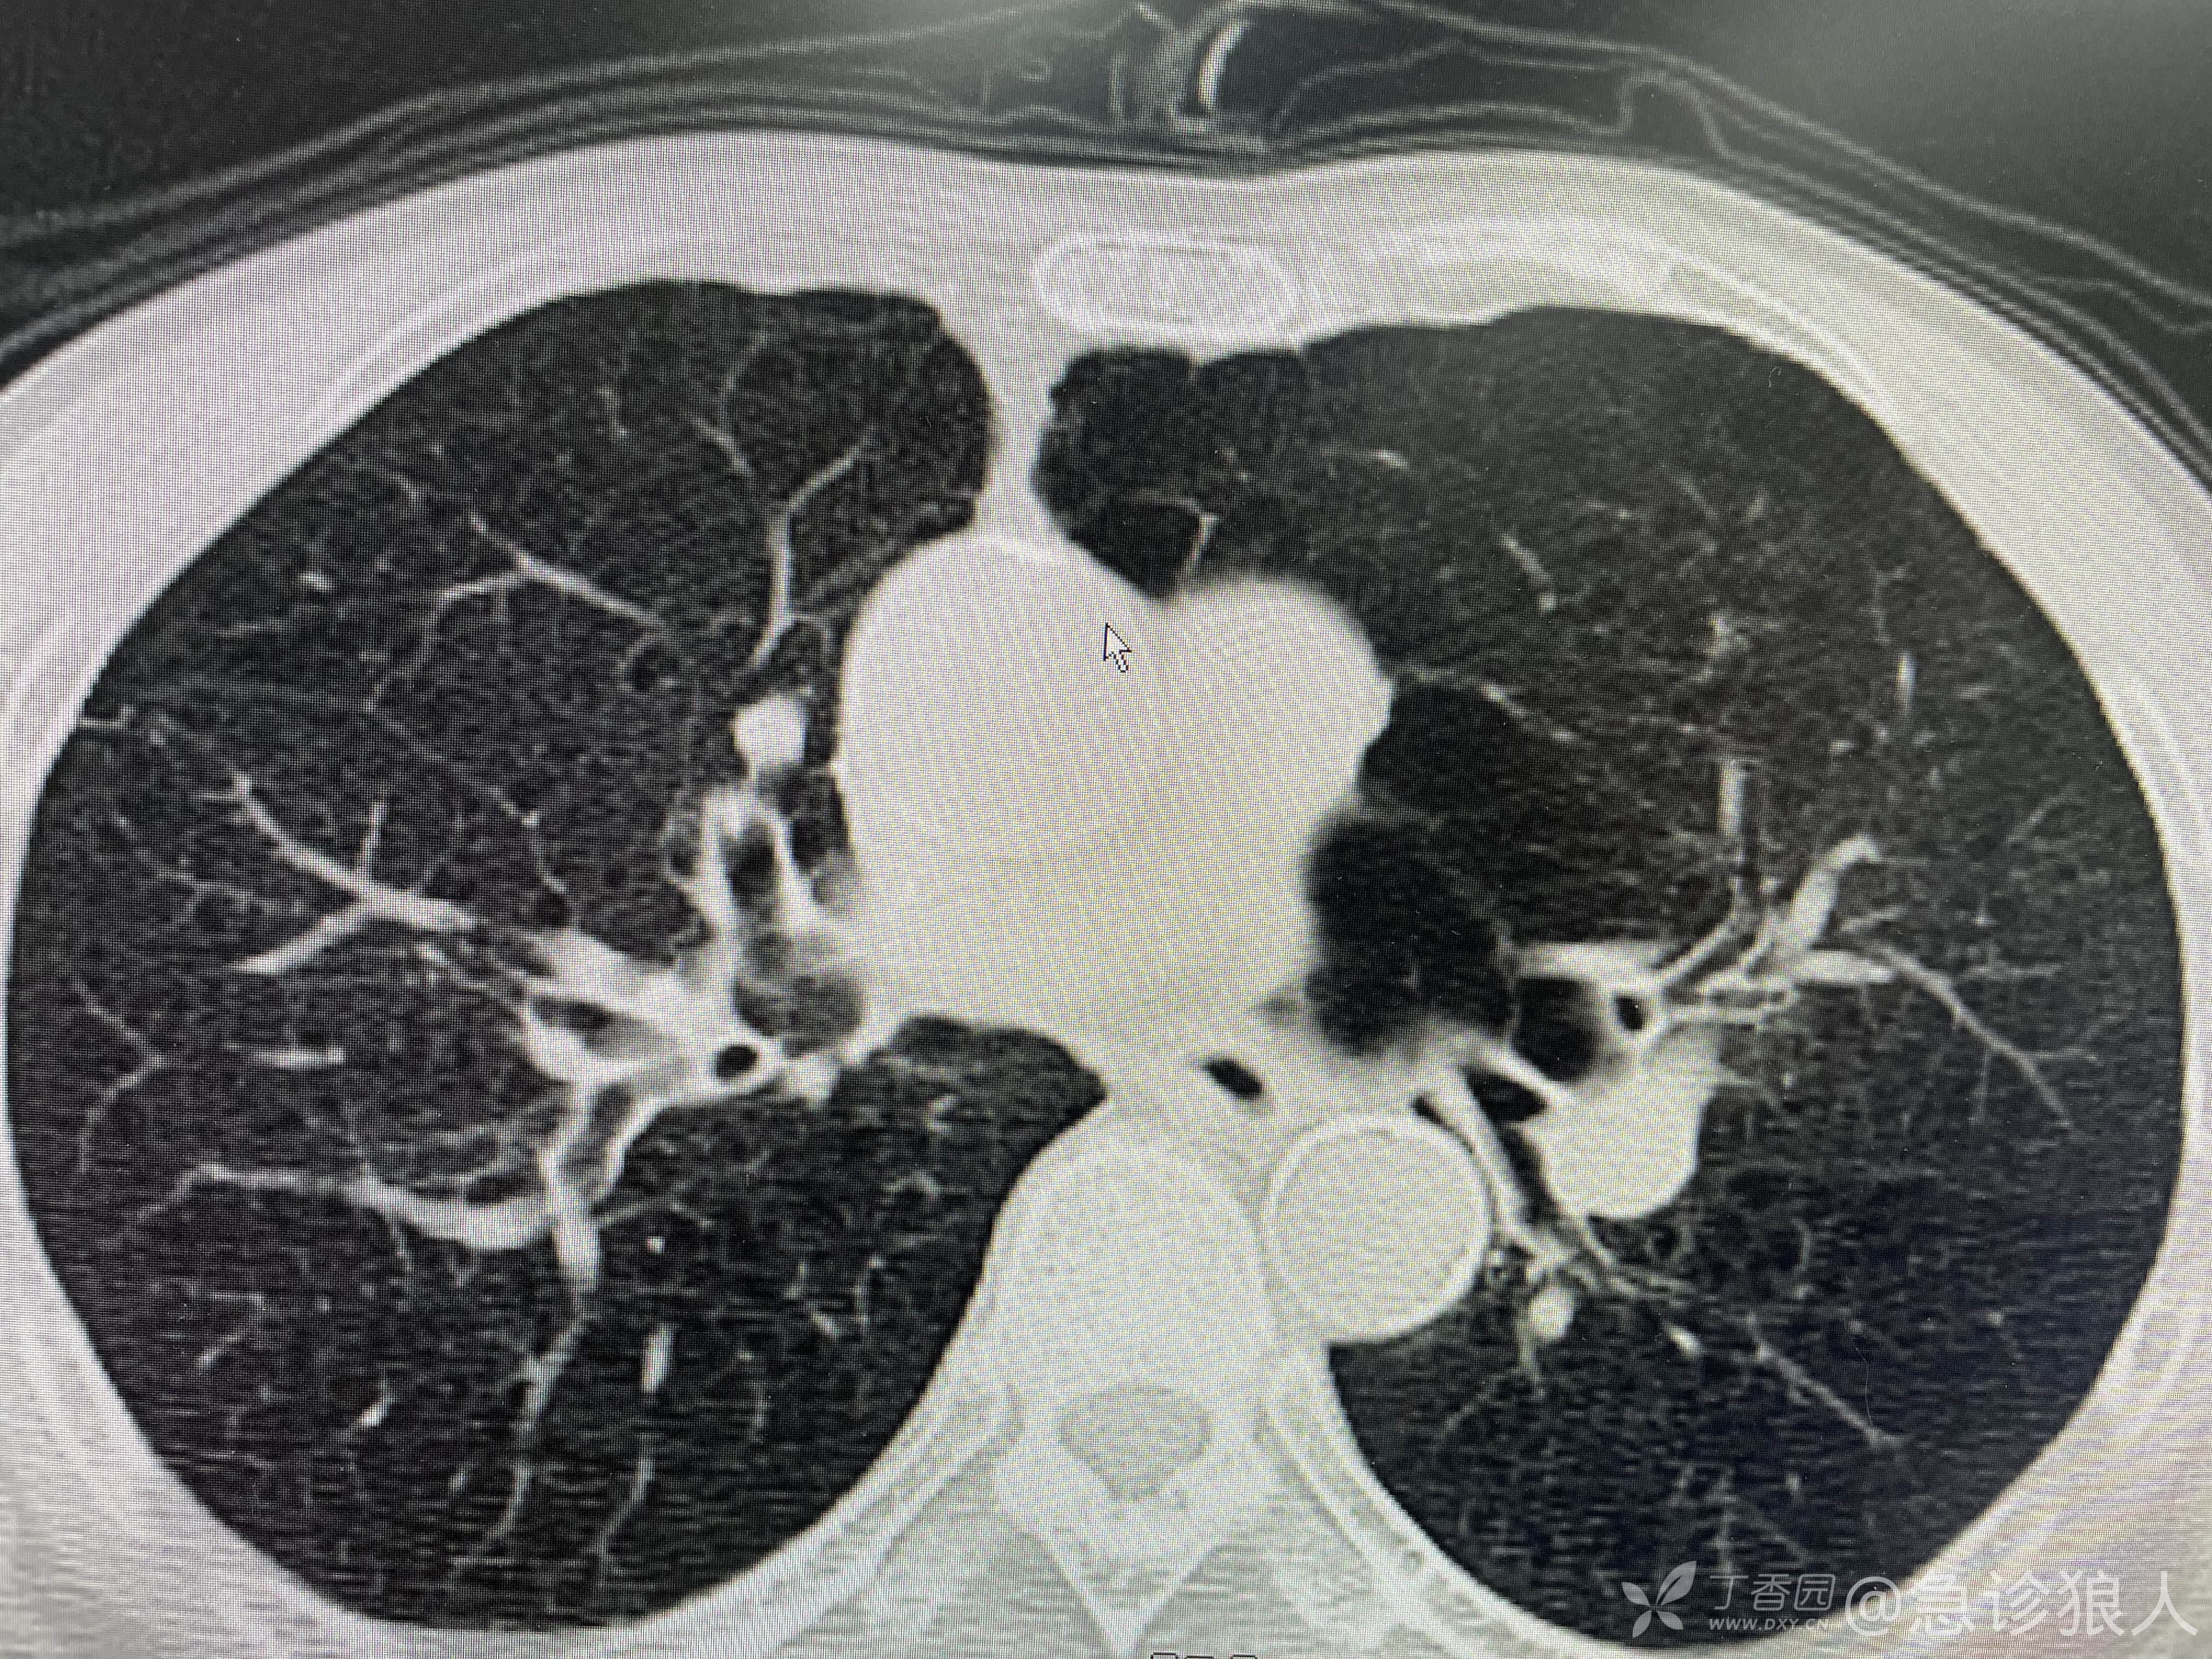

患者男60岁,5年前肺叶切除病史,具体原因不详。

继续死磕化验,心率快、血压低、D二聚体高,症状憋气,不会肺栓了吧!

“也不是这么说,我给你们讲讲他现在的情况。头晕、憋气、恶心、呕吐、腹痛,症状涵盖了神经系统、消化系统、呼吸系统。看他CT肺气肿,肯定老慢支有了。腹部Ct,肝脏结构变了,脂肪肝这么重,还这么瘦,应该是个酒精肝,肝硬化,平时喝酒很多吧?”

恶心、呕吐、头晕,这不就是喝多了!憋气是老慢支,腹痛是因为酒精肝肝硬化腹水,隐隐地痛。所有的检查都能解释!